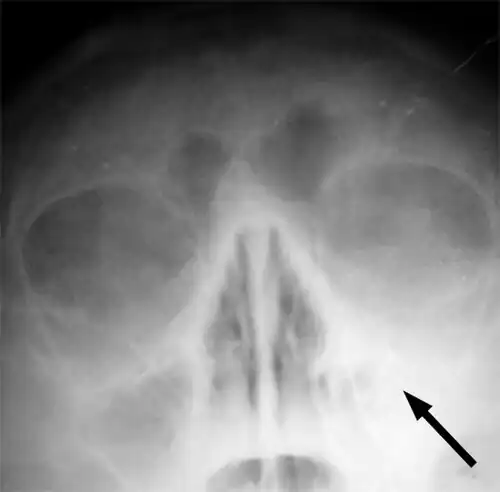

Imaging by either X-ray, CT, or MRI is generally not recommended unless complications develop.[66] Pain caused by sinusitis is sometimes confused for pain caused by pulpitis (toothache) of the maxillary teeth, and vice versa. Classically, the increased pain when tilting the head forwards separates sinusitis from pulpitis.[68]

For cases of maxillary sinusitis, limited field CBCT imaging, as compared to periapical radiographs, improves the ability to detect the teeth as the sources for sinusitis. A coronal CT picture may also be useful.[60]

X-ray of left-sided maxillary sinusitis marked by an arrow. There is a lack of air transparency, indicating fluid in contrast to the other side.